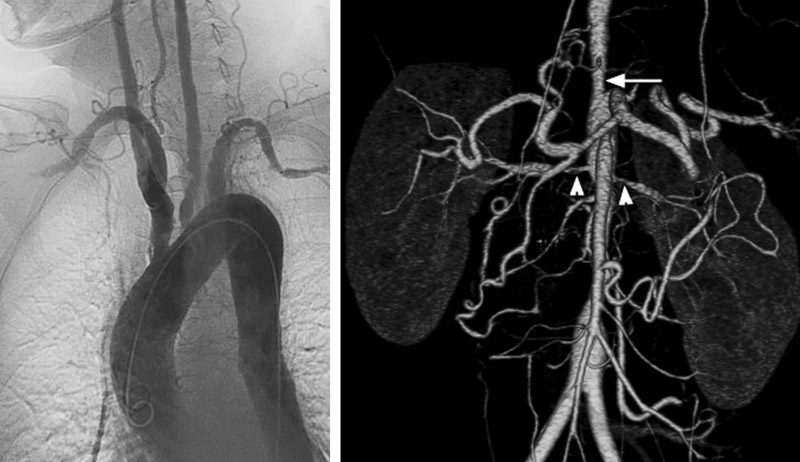

Ну и наконец, пожалуй, самая редкая причина (но очень важная!) - болезнь Такаясу. Это системный васкулит (воспалительное поражение аорты и ее ветвей, а также крупных артерий), который может приводить в итоге воспалительного процесса к резкому сужению просвета сосудов. Откуда и возникает разница в уровне АД на руках, т.к. поражение чаще всего не симметричное. Почему, собственно, болезнь получила другое название - "болезнь отсутствия пульса" - просвет артерии может полностью облитерироваться. Чаще всего эти пациенты - женщины молодого возраста, от 15 до 30 лет (я о начале болезни, т.к. в наши дни благодаря лечению такие женщины могут доживать до преклонного возраста). В комментариях к одной из моих статей читательница мне написала, что вот именно так, измеряя АД на обеих руках, врач заподозрил болезнь Такаясу у кого-то из ее родственников. Впоследствии диагноз подтвердился. Но подчеркну - это очень редкий случай, т.к. сама болезнь в наших краях крайне редка (в Японии, например - чаще).